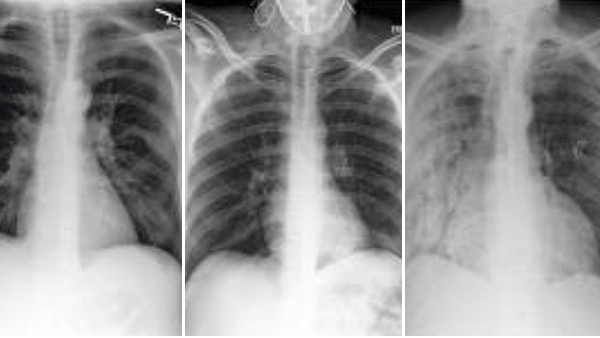

Different x-rays and CT scans displayed

AI Sees Race in X-Rays

Researchers from Emory University, MIT, Purdue University, and other institutions found that deep learning systems trained to interpret x-rays and CT scans also were able to identify their subjects as Asian, Black, or White.